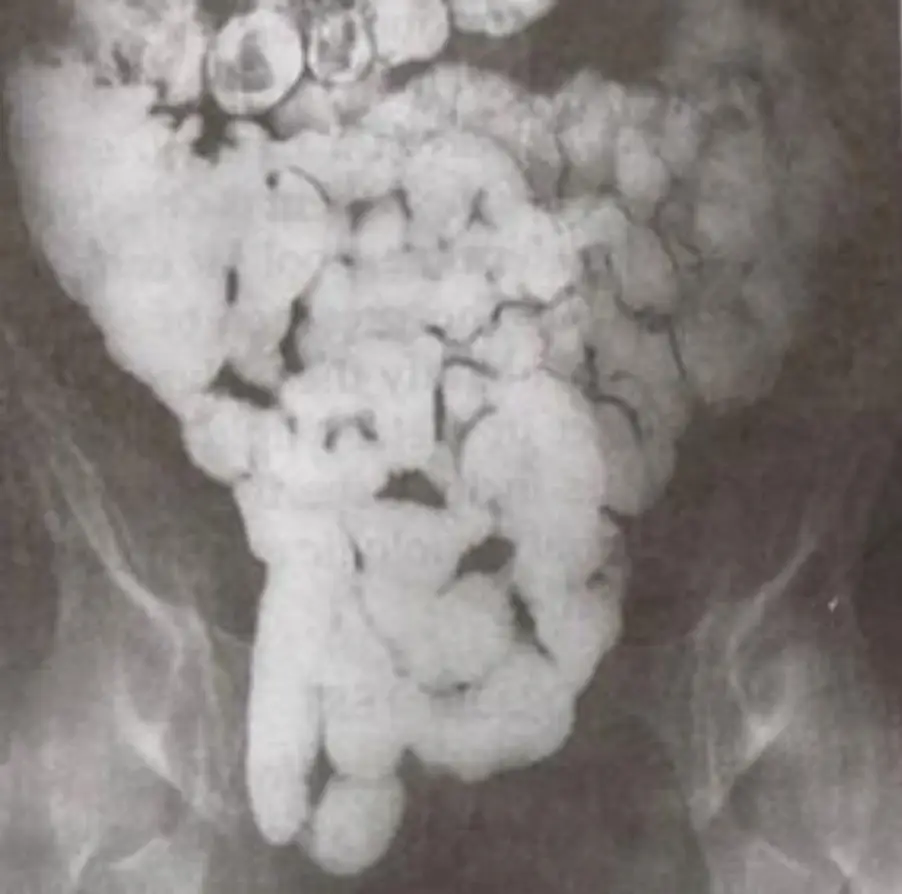

圖B:黏膜呈現不規則的粗糙、絨毛樣或「shaggy」外觀,潰瘍邊緣鈍化,局部黏膜皺襞紊亂;缺乏顯著的節段性狹窄或長段線狀潰瘍。

圖D:可見小腸中段持續性、均勻細長狹窄通道,整段黏膜紋理大致平滑;近端迴盲部或空迴部輕度不張或擴張,遠端未明顯充盈—典型「string sign(string sign of Kantor)」,代表長段炎症纖維化導致管腔固定性狹窄。